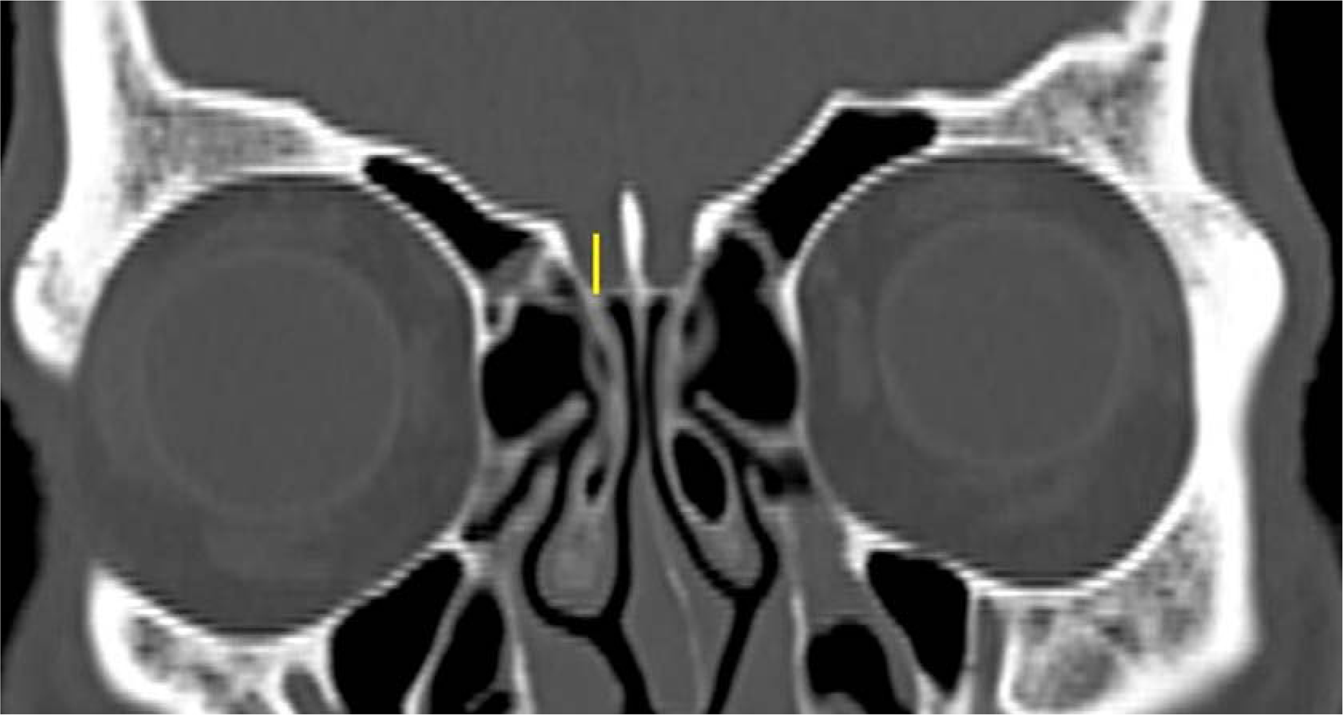

Figure 3

Keros classification7 was assessed according to the depth of the cribriform plate, measured as the vertical height of the olfactory fossa in the CT coronal plane and classified as type 1, 2 and 3.